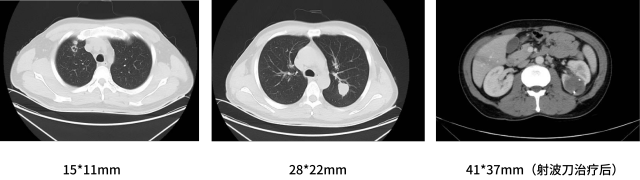

影像学检查--基线

2020-12-14:

双肺转移